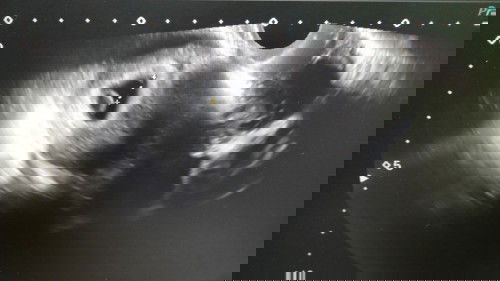

Semalam saya banyak berjalan, bila nk buang air kecil ada seketul darah jth dkt seluar dalam. Bila balik rumah sy kencing seketul jgk kluar xpi x byk drh. Saya ke hospital check dan scan kantung msih ada.. scan dkt perut x nmpk tp scan melalui bawah nampak kecik.. saya tanya doktor adakah saya gugur.. doktor x bg kepastian dia suruh saya balik rumah dan dtg dlm 2 mggu lagi. Ada tak kawan2 semua seperti saya?